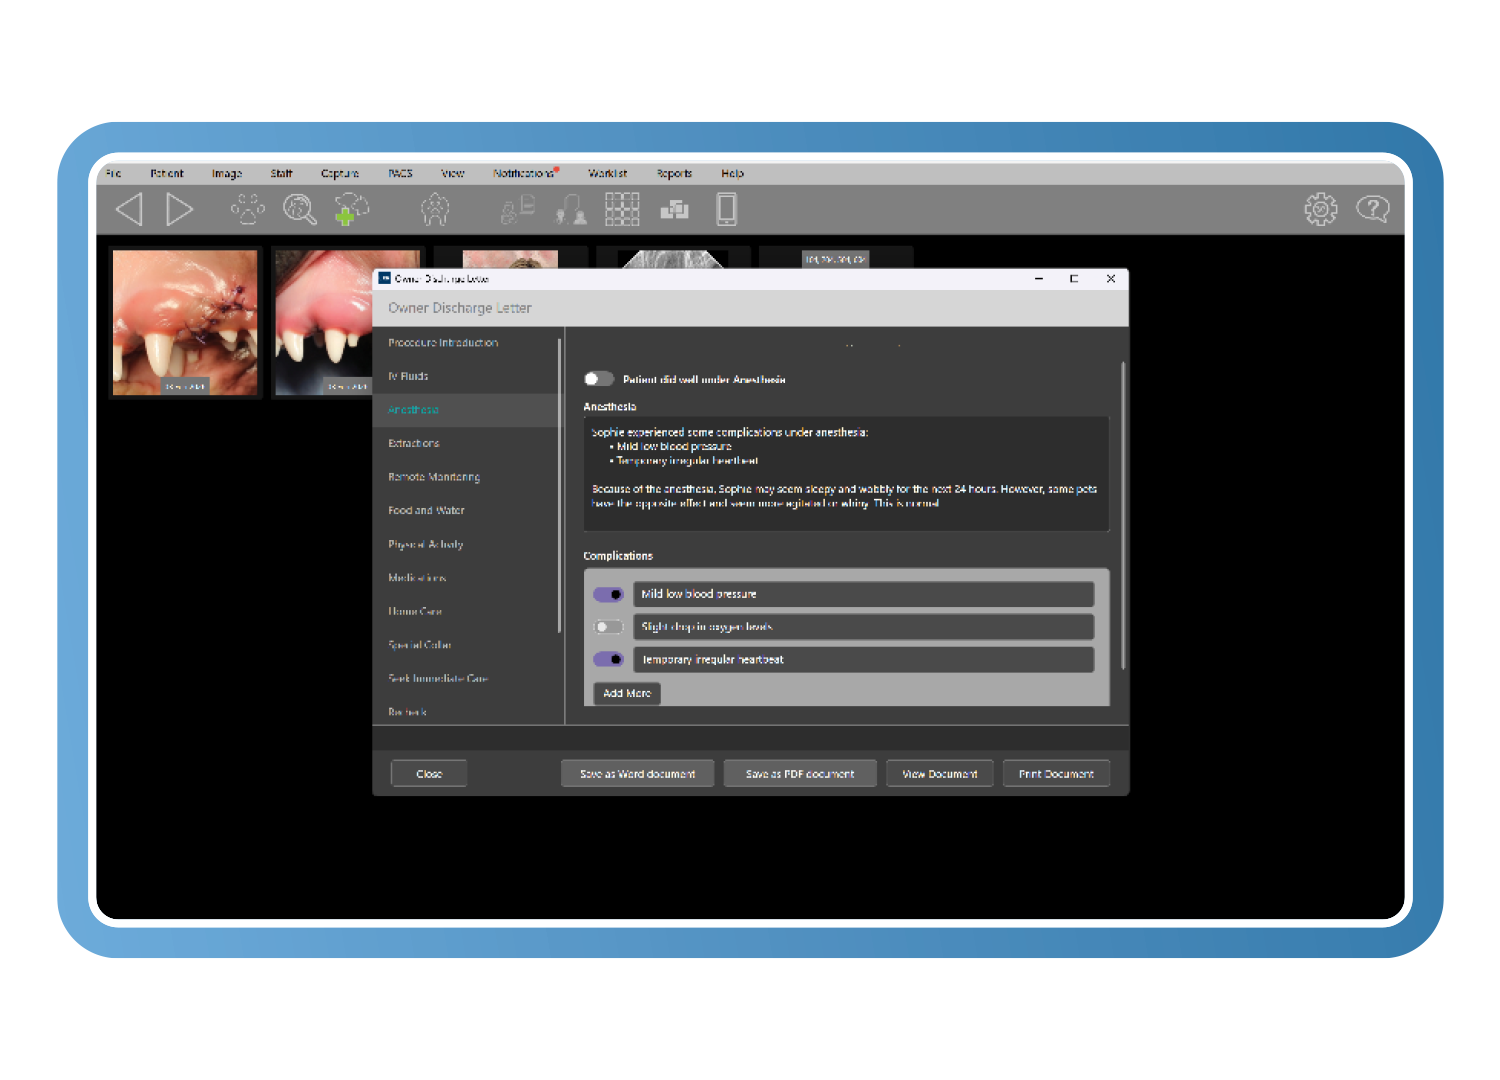

Alta clínica y monitoreo remoto según mejores prácticas

Cree cartas de alta personalizables alineadas con las directrices de la AAHA, que incluyen explicaciones en lenguaje claro, imágenes de antes y después y contenido asistido por Clarity. El monitoreo remoto de heridas integrado permite a los propietarios enviar imágenes después del tratamiento, reduciendo las revisiones innecesarias mientras se mantiene la supervisión clínica.